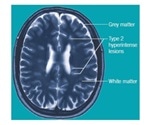

The efficacy of an array of antidepressant drugs, specifically the selective serotonin reuptake inhibitors (SSRIs), has made it possible to describe the physiological roles of SERT in the brain. It is unquestionable that the transporter has an impact on depression, although its accurate function is still a debatable topic. More evidence arises from the genetic difference that takes place upstream of the SERT coding sequence: the 5-HTT gene-linked polymorphic region (5-HTTLPR). A range of repeated units integrated inside this sequence creates a promoter region that regulates the expression of SERT72,73. Within this region, one common polymorphism is a 44 base pair deletion, indicated as a short form (S) for the gene, together with variations of a long form (LA and LG). The short form allele lowers the expression and function of SERT in relation to the long forms72,74. However, it has been reported that LG may lead to SERT expression similar to the short form variant75, and the short form allele may not be related to reduced SERT levels in the adult brain76, further complicating the research field. Even if one short form allele is present in individuals, it predisposes them to depressive episodes.

In further support from in vivo imaging, expression of SERT is reduced within the brainstem77, amygdala and midbrain78 in patients suffering from depression. Several reports associate the expression of SERT with the brains of suicide victims, although this area continues to be a controversial topic79. However, SERT knockout mice show behavioral abnormalities in relation to anxiety and depression80,81.